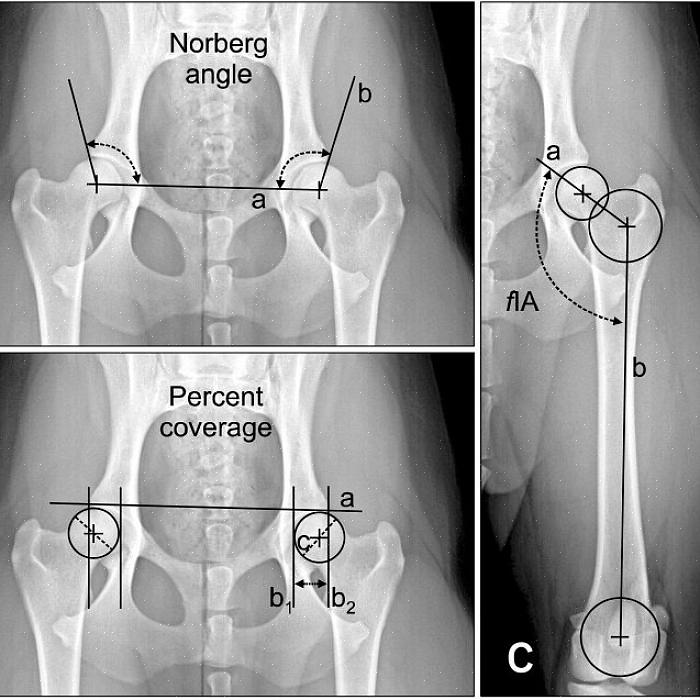

Når du tar med hunden din til veterinæren for tegn på hoftesmerter eller hofteleddsdysplasi, vil veterinæren din begynne med å undersøke hunden din grundig. Dette vil inkludere manipulering av leddene og observasjon av hundens ganglag. Deretter vil veterinæren sannsynligvis anbefale røntgenbilder (røntgenbilder) av hundens hofter, bakben og muligens ryggraden. Riktig plassering er ekstremt viktig for å få en nøyaktig diagnose. Dette kan være vanskelig for mange hunder, spesielt de som har smerter. Mange hunder trenger å bli bedøvet for riktig posisjonerte røntgenbilder.

Både undersøkelsen og røntgenbilder er avgjørende for riktig diagnostisering av hoftedysplasi hos hund. Vær oppmerksom på at andre ortopediske problemer kan bli oppdaget som den primære årsaken til hundens tegn. Hoftedysplasi kan oppdages tilfeldig, men det kan være et annet problem som krever behandling, for eksempel korsbåndskade eller patellaluksasjon. Det er derfor undersøkelsen er så viktig.

Anerkjente oppdrettere av disse predisponerte hunderasene vil ofte få hundenes hofter screenet og sertifisert via Orthopedic Foundation for Animals eller Pennhip før de avler dem. Screening innebærer å ta nøyaktig posisjonerte røntgenbilder av hoftene, vanligvis gjort under sedasjon. Hunder kan sertifiseres etter fylte to år. Imidlertid kan røntgenbilder tatt så tidlig som fire måneders alder avsløre en hunds mottakelighet for hofteleddsdysplasi.